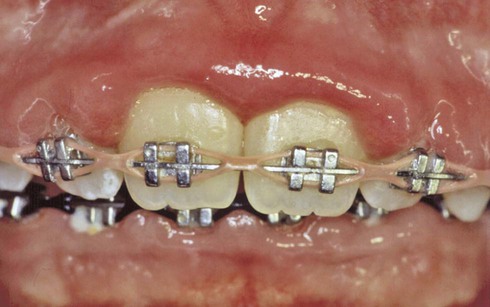

| Local factors | Overhanging restorations, subgingival placement of crown margins, orthodontic appliances, and removable partial dentures also may contribute to the progression of periodontal disease. |

Gingivitis is found only in the epithelium and in gingival connective tissues. No tissue recession or loss of connective tissue or bone is associated with gingivitis (Fig. 14-4). Other types of gingivitis are associated with puberty, pregnancy, and the use of birth control medications (Box 14-2 and Fig. 14-5). Orthodontic appliances tend to retain bacterial plaque and food debris, resulting in gingivitis (Fig. 14-6). Instruction regarding proper home care is a critical part of orthodontic treatment (see Chapter 60).